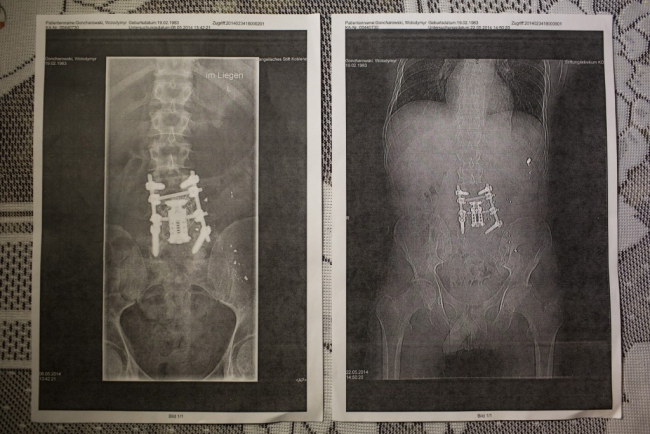

Володимир Гончаровський

Йому 31 рік, одружений, батько чотирьох дітей, був тяжко поранений 20 лютого 2014 року пострілами - двічі у спину і в праву руку. Він рятував поранених учасників Євромайдану, в яких стріляли правоохоронці на вулиці Інститутській в Києві. Йому робили численні операції в Україні та Німеччині, але його стан залишається надзвичайно складним.

У нього діагностували гепатит С. Володимир думає, що міг підхопити вірус під час отримання медичної допомоги після поранення на Євромайдані.